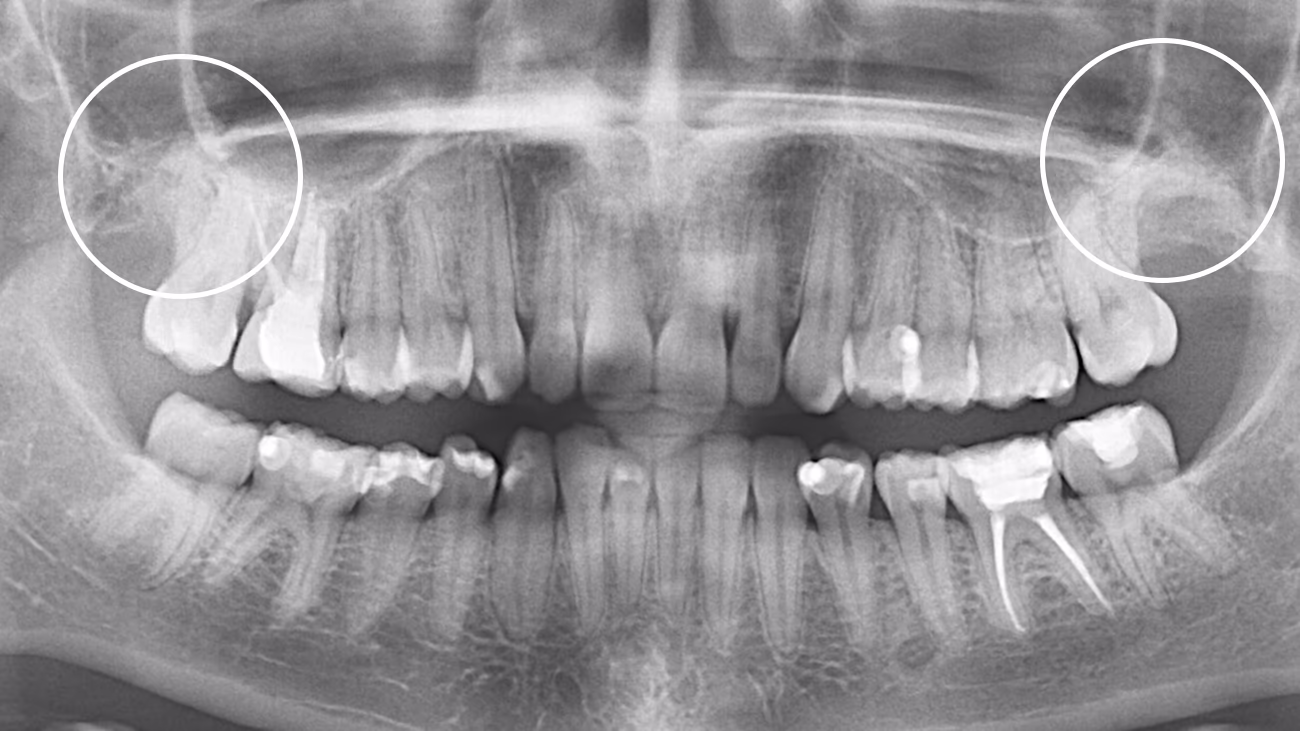

Так. КТ є обов’язковою для точного та безпечного видалення зуба мудрості.

3D-діагностика дозволяє визначити:

• положення зуба

• напрямок росту

• особливості коренів

• близькість до нижньощелепного нерва або верхньощелепної пазухи

У Sergatiy Dental Clinic КТ є обов’язковою перед видаленням зуба мудрості. Без КТ значно підвищуються ризики ускладнень.